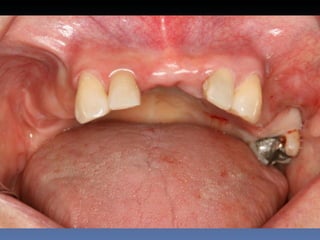

BOX 4

Maria Balbina Gonçalves

Idade – 52 anos

Sexo – Feminino

Raça – Caucasiana

ASA – II

Data- 27-04-2012

Diagnóstico: Atrofia maxilar vertical

posterior bi-lateral; atrofia da pré-maxlia.

Plano de tratamento: “Sinus-lift” bilateral , reabilitação

da pré-maxila com ROG - regeneração óssea guiada,

osso proveniente de Fêmur -Homógeno Fresco-

congelado,       para instalação de implantes endo-

ósseos, e reabilitação protética fixa.